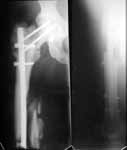

The nail has just been removed through old incisions. The neck is not healed, the shaft is partially healed (image 2).

The biggest problem here is the femoral neck nonunion in a 44 yo obese (?weight) patient. No femoral head AVN apparent on plain xray but a significant fracture gap with a verticle fracture line on AP. If you can get that to heal you will be doing her a great service. The femoral shaft is still secondary.